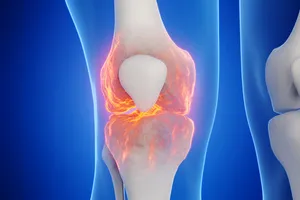

무릎 인공관절수술이란?

무릎 인공관절수술은 심각하게 손상된 무릎 관절을 인공 관절로 대체하는 수술입니다. 퇴행성 관절염, 외상성 관절염 등으로 인해 무릎 통증이 심하고, 일상생활에 지장을 초래하는 경우, 인공관절 수술을 통해 통증을 완화하고 운동 기능을 회복할 수 있습니다.